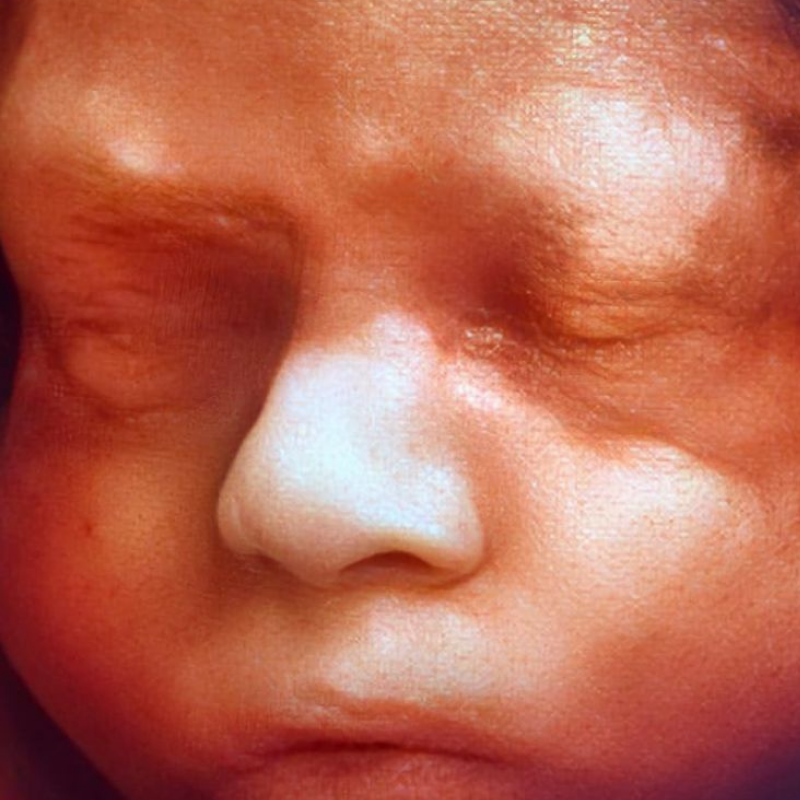

Ocho de cada mil bebes nace con algún defecto cardíaco congénito. Estas anomalías se producen por un desarrollo anormal del corazón durante el embarazo y pueden consistir en defectos de sus paredes o válvulas, o de los vasos sanguíneos que entran o salen de él.